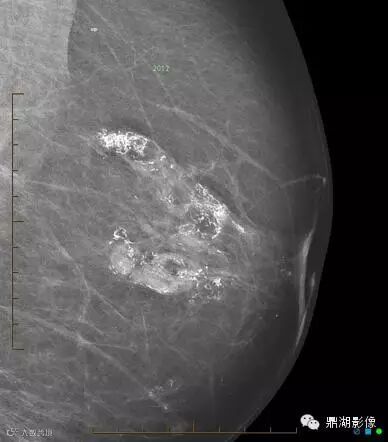

女,60,双侧乳房成形术数年,发现无痛性肿块数月。

双侧乳腺可见环状钙化

临床诊断:乳腺脂肪坏死

脂肪坏死误诊为乳腺癌的比例最高,乳腺脂肪坏死是显性或非显性乳腺创伤后的一种病理改变,病变本质是坏死组织在酶解液化过程中诱发以单核巨噬细胞浸润为主的肉芽肿性炎症。乳腺脂肪坏死误诊为乳腺癌的原因主要有: 临床表现与乳腺癌相似,缺乏特征性临床乳腺癌和脂肪坏死大多表现为肿物,临床表现为肿块的脂肪坏死与乳腺癌不易区分,脂肪坏死的共同特点是肿块部位表浅,密度低于癌变密度且不均匀,边界清楚,可伴有索条影,无浸润,有时脂肪坏死可伴有钙化,几乎均为散在的点状钙化,文献报道,X 线摄片乳腺内环状钙化可能是脂肪坏死的一个特征性改变。而乳腺癌的钙化一般为成堆,密集分布,多形性细小钙化。

脂肪坏死临床及X线表现有如下特点:① 多有外伤、医源性损伤的病史,少数由导管扩张、炎症引起;② 临床上多为无痛性肿块和结节,质地偏硬,边缘欠清晰,少数有压痛;③伴有淋巴结肿大者,多为反应性增生,淋巴结光滑、质软、活动、无融合;④ 随访观察肿块无增大,反而逐渐缩小;⑤X线上脂性囊肿伴蛋壳样钙化以及皮下脂肪层内斑片状、星芒状、索条状及网状影为脂肪坏死的特征性表现。